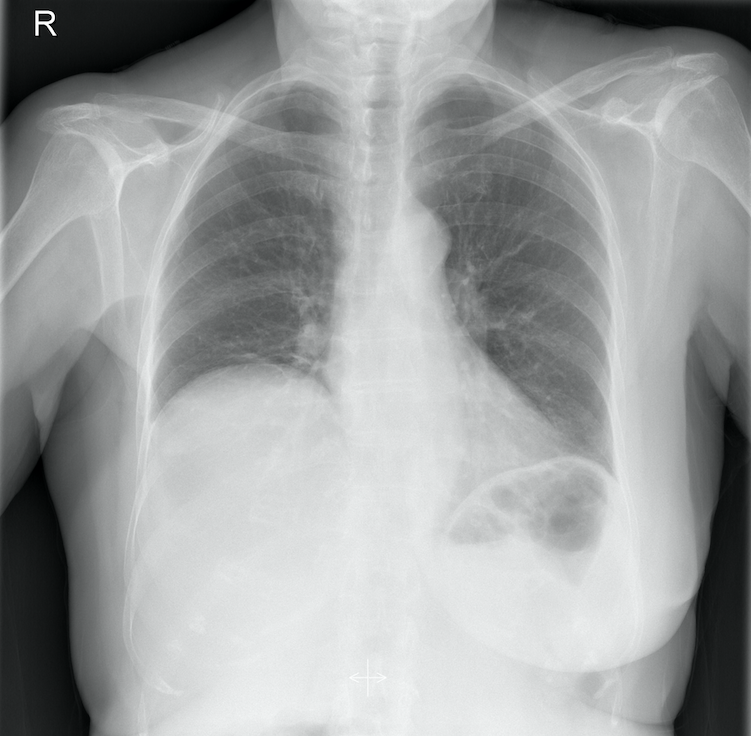

Mujer de 85 años, hipertensa en tratamiento con ARA-II, fue valorada por la mañana en su domicilio debido a dolor torácico no opresivo que aumentaba al inspirar de 24 horas de evolución. Acudió más tarde al punto de atención continuada (PAC) porque el dolor era intenso a pesar de la analgesia pautada. Indagando mejor, el dolor se localizaba en hipocondrio derecho irradiándose al hombro ipsilateral sin acompañarse de fiebre, ictericia, náuseas, vómitos ni alteraciones deposicionales. El ECG fue normal. La auscultación cardio-pulmonar anodina. Destacaba una hepatomegalia dolorosa de dos traveses de dedo con Murphy dudoso. Se derivó al Servicio de Urgencias Hospitalarias (SUH) para valoración. Los datos analíticos de laboratorio se encontraban dentro de límites normales. Se solicitó radiografía de tórax y abdomen que mostraron elevación de hemidiafragma derecho y se dió el alta hospitalaria con el diagnóstico de: «dolor abdominal inespecífico sin datos de alarma» con tratamiento sintomático.